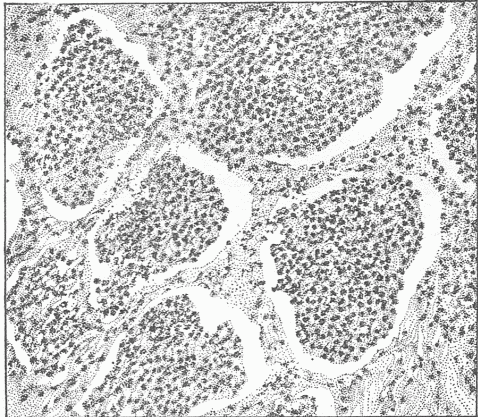

The external surface passes into the interior of the body forming two surfaces, one of which, the intestinal canal, communicates in two places, at the mouth and anus, with the external surface; and the other, the genito-urinary surface, which communicates with the external surface at one place only. The surface of the intestinal canal is much greater in extent than the surface on the exterior, and finds enormous extensions in the lungs and in the great glands such as the liver and pancreas, which communicate with it by means of their ducts. The extent of surface within the lungs is estimated at ninety-eight square yards, which is due to the extensive infoldings of the surface [Fig 6], just as a large surface of thin cloth can, by folding, be compressed into a small space. The intestinal canal from the mouth to the anus is thirty feet long, the circumference varies greatly, but an average circumference of three inches may safely be assumed, which would give between seven and eight square feet of surface, this being many times multiplied by adding the surfaces of the glands which are connected with it. A diagram of the microscopic structure of the intestinal wall shows how little appreciation of the extent of surface the examination with the naked eye gives [Fig. 7]. By means of the intestinal canal food or substances necessary to provide the energy which the living tissue transforms are introduced. This food is liquefied and so altered by the action of the various fluids formed in the glands of the intestine and poured out on the surface, that it can pass into the interior of the body and become available for the living cells. Various food residues representing either excess of material or material incapable of digestion remain in the intestine, and after undergoing various changes, putrefactive in character, pass from the anus as feces.

Fig. 7.—A Section Of The Small Intestine To Show The Large Extent Of Surface. (a) Internal surface. The small finger-like projections are the villi, and between these are small depressions forming tubular glands.